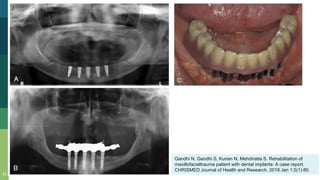

Gandhi N, Gandhi S, Kurian N, Mehdiratta S. Rehabilitation of

maxillofacialtrauma patient with dental implants: A case report.

CHRISMED Journal of Health and Research. 2018 Jan 1;5(1):80.